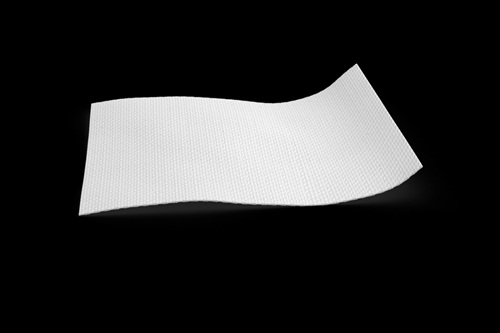

* 0.2 mm thick, highly condensed

* Trim with curved scissors when it is dry

* OSSIX Plus should be hydrated with saline for 30 seconds

* Do not suture through the membrane. Fixation options: no fixation at all / with periosteal sutures, or tacking without stretching